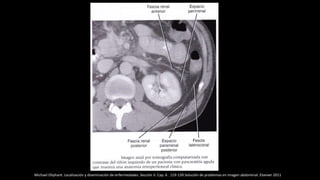

ESPACIOS ABDOMINALES

• EXTRAFASCIAL: Entre la piel y fascia superficial muscular (contiene fundamentalmente

Tejido celular subcutáneo.

• INTRAFASCIAL: Entre la fascia superficial muscular y la fascia transversalis (contiene

músculos de la pared)

• EXTRAPERITONEAL (retroperitoneal):Entre el peritoneo parietal y por dentro de la

fascia transversalis : grasa properitoneal, Intracapsular , pararenal anterior y posterior , intrarenal

• SUBPERITONEAL : Limitado por las dos hojas de peritoneo visceral que recubren los

diferentes ligamentos (hepatoduodenal, mesenterio, etc.)

• INTRAPERITONEAL: Por dentro del peritoneo comprende las cavidades peritoneales: una

mayor y menor.